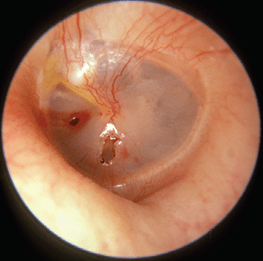

Tymp Perforation – Before